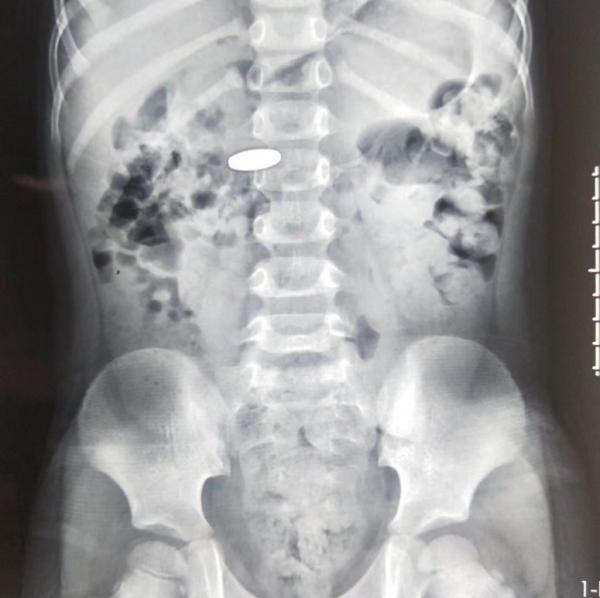

1、最常見的“急診玩具”——硬幣。

作為名副其實的“吞金獸”,硬幣一直是小朋友們的最愛,常年高居兒童呼吸道和消化道異物榜首。這主要是因為孩子的咽喉部保護性反射發育不完善,當孩子將硬幣、堅果、玻璃珠、紐扣電池、玩具零部件等這種體積小,且形狀圓頓的玩具含在嘴裡時,孩子的咽喉部不能有效阻擋異物。這類異物如果進入呼吸道,可引起呼吸困難或反覆肺部感染,從而出現氣促、發熱、咳嗽等症狀。若進入消化道,多可自行排出,但小部分可停留在消化道狹窄處,導致區域性粘膜損傷或消化道梗阻,甚至破裂穿孔,從而出現頑固性惡心、嘔吐、胸痛、腹痛、腹脹等症狀。